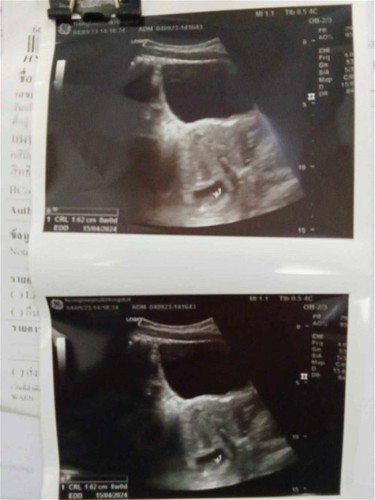

บ้านนี้8วีคแล้วค่ะท้องใหญ่มาก จะรุ้เพศตอนกี่วีคค่ะ.